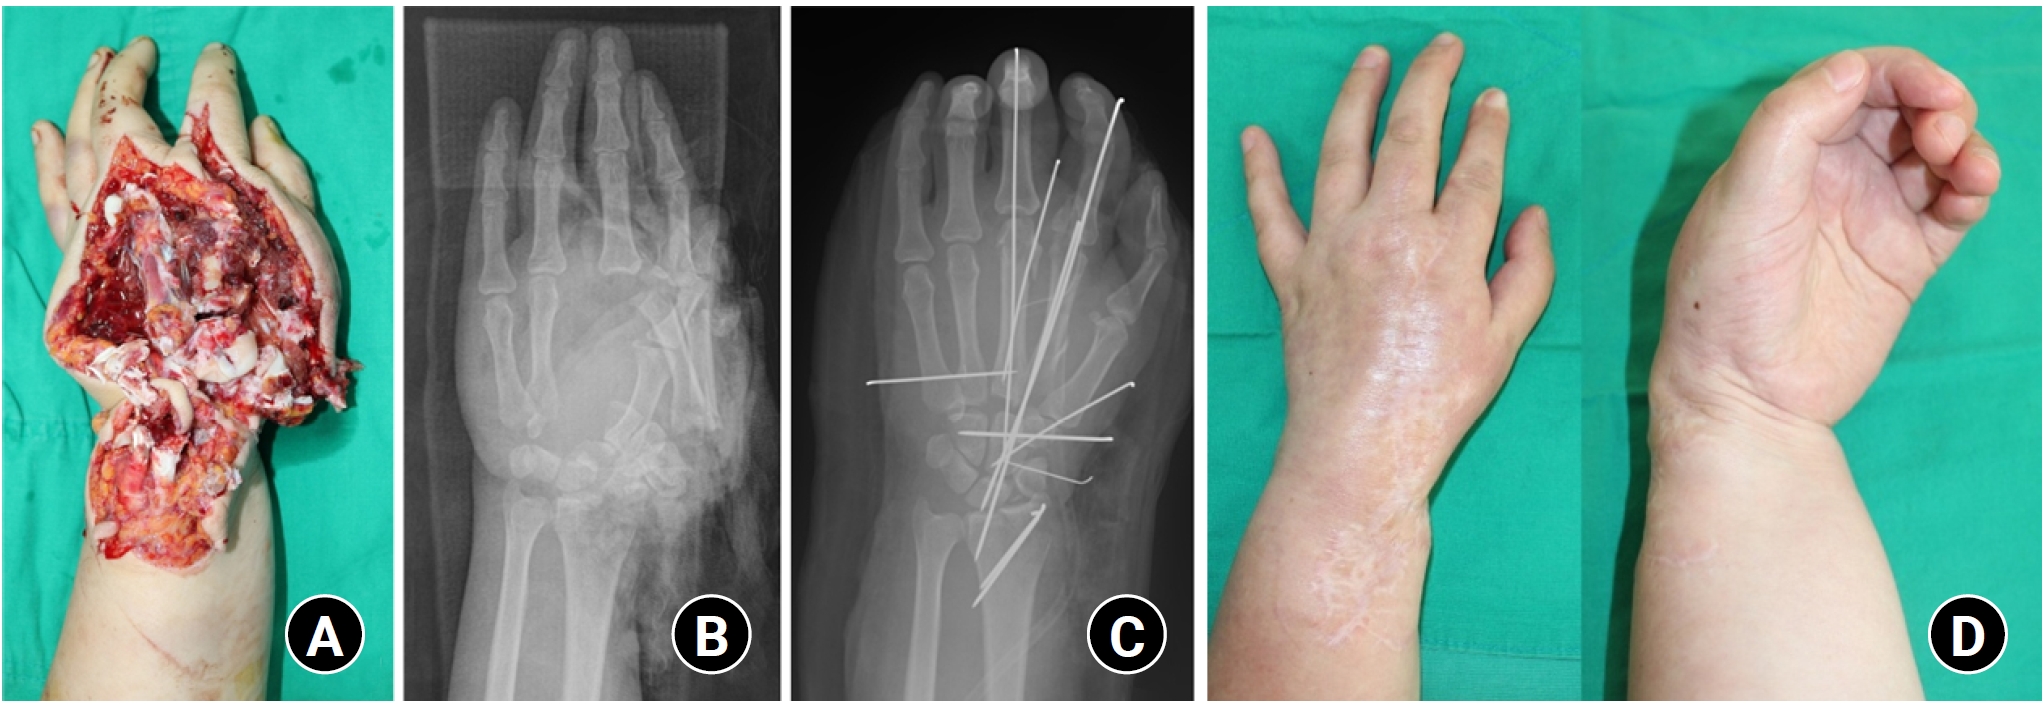

Stiffness is the most common complication during the treatment of hand fractures and one of the most challenging complications to treat [2]. The risk of stiffness is higher in cases of severe comminuted fractures, open fractures, or crush injuries with extensive soft tissue damage around the fracture site (Fig. 1) [3]. Especially, proximal phalangeal fractures have a higher risk of stiffness compared to other hand fractures, so immobilization with a splint for more than 4 weeks can potentially cause stiffness [2]. Therefore, the key principle is to achieve sufficient stability to permit early protected active motion; rigid internal fixation is one way to accomplish this, but selected stable fracture patterns can also be managed nonoperatively with functional support while still allowing early mobilization [4,7-9]. In particular, uncomplicated fifth metacarpal neck fractures and selected metacarpal shaft fractures without rotational deformity or unacceptable shortening/angulation can often be treated functionally (e.g., buddy taping/soft wrap) with early protected mobilization, achieving outcomes comparable to more restrictive immobilization in appropriate patients [7-9]. A common mistake orthopedic surgeons make in treating hand fractures is unnecessarily prolonging rigid splint immobilization solely to observe radiographic callus formation. Phalangeal fractures typically heal within 4 weeks, but callus formation may not be visible on plain radiographs at that time [2]. Therefore, rather than continuing rigid immobilization, gentle active motion exercises of the joints can be carefully initiated if there is no focal tenderness or pain at the fracture site on physical examination at approximately 4 weeks [2]. If there are concerns about loss of reduction because radiographic healing appears insufficient, using a removable splint during active joint exercises and wearing the splint during other activities can be a practical alternative to prolonged rigid immobilization [2]. Early joint motion is essential, especially in hand crush injuries [4]. When a crush injury occurs to the hand, it damages all structures from the skin to the bone, causing severe swelling and stiffness of the soft tissues [3]. Therefore, early joint motion helps minimize swelling and soft tissue stiffness, but rigid fracture fixation is necessary to allow early motion [3].

Fig. 1.

(A) A case with multiple open hand fracture-dislocations and severe soft tissue injury. (B) Preoperative plain radiograph shows multiple hand and wrist fractures and dislocations. (C) A postoperative plain radiograph shows that temporary K-wire fixation was performed to maintain bony alignment and manage soft tissue injury. (D) The last follow-up photograph shows severe finger stiffness and permanent disability.

Fig. 1. (A) A case with multiple open hand fracture-dislocations and severe soft tissue injury. (B) Preoperative plain radiograph shows multiple hand and wrist fractures and dislocations. (C) A postoperative plain radiograph shows that temporary K-wire fixation was performed to maintain bony alignment and manage soft tissue injury. (D) The last follow-up photograph shows severe finger stiffness and permanent disability.